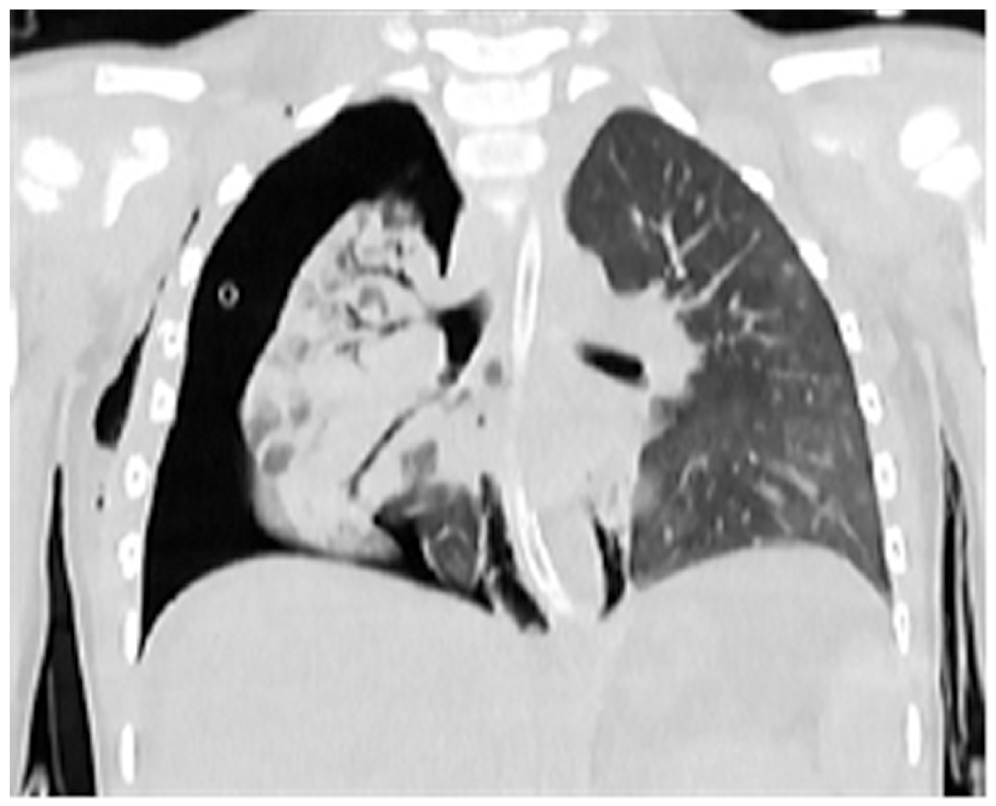

При поступлении выполнена спиральная компьютерная томография (СКТ) в режиме «Whole body». На основании клинико-инструментального обследования с учётом анамнестических данных и данных первичного стационара был сформулирован диагноз: «Тяжёлая сочетанная травма [оценка по шкале тяжести травмы (Injury Severity Score) 41 балл]; закрытая тяжёлая ЧМТ [по шкале оценки тяжести изолированных повреждений (Abbreviated Injury Scale, AIS) AIS-4]; ушиб головного мозга тяжёлой степени; перелом левой височной, теменной и затылочной костей; закрытая травма груди (AIS-4); множественные переломы рёбер (2–8) справа; ушиб левого лёгкого средней степени тяжести; разрыв правого лёгкого; большой напряженный пневмоторакс справа (AIS-4); закрытая травма живота (AIS-3); разрыв правой доли печени; гемоперитонеум; травматический шок 3 степени». Ребёнок был госпитализирован в отделение реанимации, где продолжена интенсивная терапия. Тяжесть состояния ребёнка была обусловлена тяжестью травматических повреждений с развитием множественной органной дисфункции в рамках синдрома взаимного отягощения. По плевральным дренажам сохранялось продувание воздуха, аускультативно определялось ослабление дыхания над всей поверхностью правого лёгкого. По данным СКТ при поступлении и рентгенографии органов грудной клетки, выполняемой ежедневно в палате отделения реанимации, сохранялось коллабирование правого лёгкого от ⅓ до ⅔ (рис. 1).

Рис. 1. Спиральная компьютерная томография при поступлении: коллабирование правого лёгкого с большим пневмотораксом.

Fig. 1. Spiral computed tomography at admission: collapse of the right lung with a large pneumothorax.